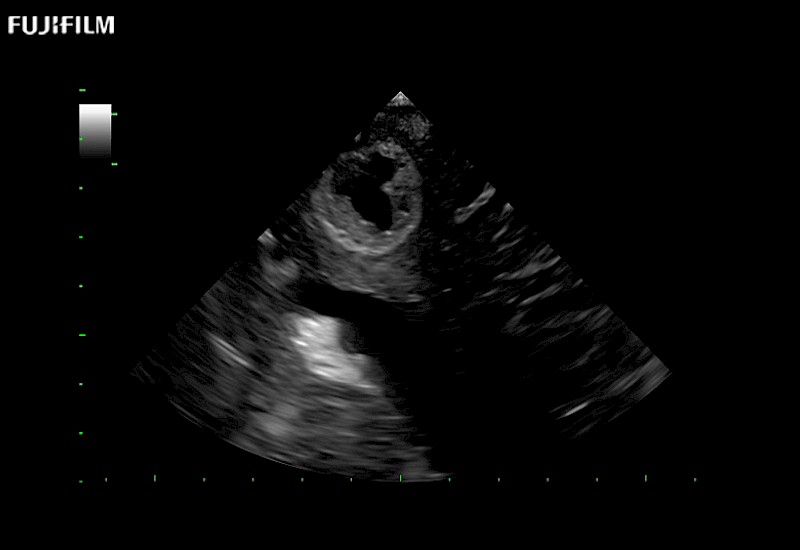

Our dedication to neurosurgery allows us to offer superior image quality, outstanding system reliability and intuitive use of cutting edge technology.

Guidance is the fundamental purpose for all of our surgical ultrasound technology. Fujifilm Healthcare is committed to designing tools that help neurosurgeons navigate inside the human body and provide the necessary information to immediately make critical surgical decisions.